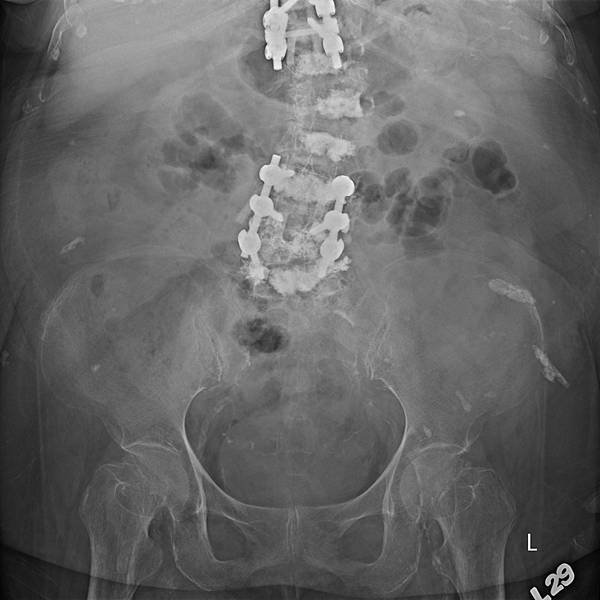

腸躁症有許多種病因,是一種大腸鏡看起來正常的慢性大腸發炎。長期便秘、腹瀉、腹脹、腹痛,不管病人陳述甚麼症狀,KUB絕對不能省掉,之前照過你還是要再照一次。CBC-DC與CRP也不能省,不時會有驚人的發現。